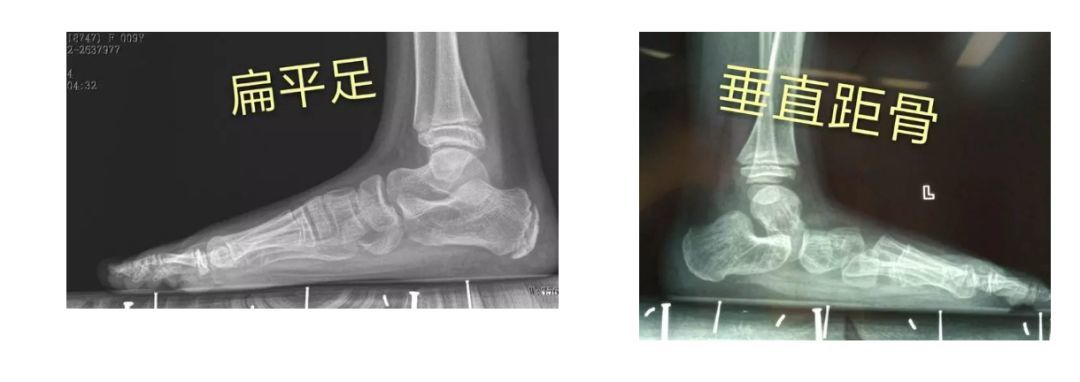

扁平足和僵硬性扁平足,需要儿童骨科医师仔细鉴别检查,特别是垂直距骨

先天性垂直距骨是一种少见的严重的先天性畸形足,又称为先天性凸形